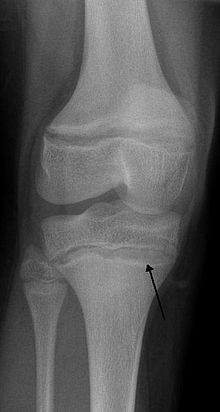

An X ray demonstrating the characteristic finding of lead poisoning in humans—dense metaphyseal lines.

One of the clinical signs of rickets that doctors look for is cupping and fraying at the metaphyses when seen on X-ray.